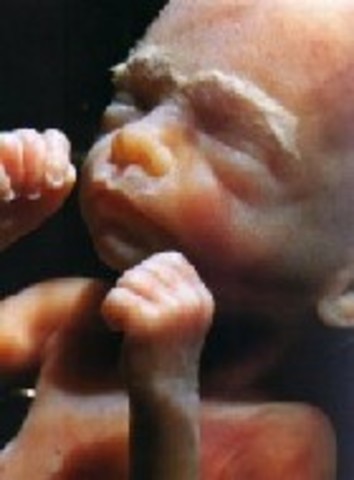

• Week 9: Fingers and Toes Form

Week 9: Fingers and Toes Form

Embryo has grown to 30mm, fingers and toes are well defined, cartilage and bones begin to form, upper lip and nose tip are being formed, tongue begins to develop, larynx is developing, eyelids are developed, main construction of heart is complete. During this week of pregnancy your baby is now swimming around in a little bag of fluid